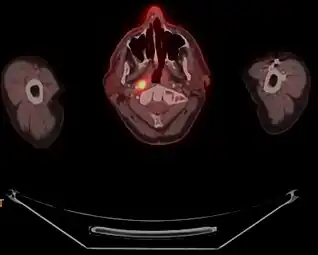

Nasopharyngeal carcinoma, also known as nasopharyngeal cancer, is classified as a malignant neoplasm, or cancer, arising from the mucosal epithelium of the nasopharynx, most often within the lateral nasopharyngeal recess or fossa of Rosenmüller (a recess behind the entrance of the eustachian tube opening). The World Health Organization classifies nasopharyngeal carcinoma in three types, in order of frequency: Non-keratinizing squamous cell carcinoma; keratinizing squamous cell carcinoma; and basaloid squamous cell carcinoma.[16] The tumor must show evidence of squamous differentiation, with the non-keratinizing type (also known as lymphoepithelioma) the tumor most strongly associated with Epstein-Barr virus infection of the cancerous cells.[17]

Staging of nasopharyngeal carcinoma is based on clinical and radiologic examination. Most patients present with Stage III or IV disease.

Stage I is a small tumor confined to nasopharynx.

Stage II is a tumor extending in the local area, or that with any evidence of limited neck (nodal) disease.

Stage III is a large tumor with or without neck disease, or a tumor with bilateral neck disease.

Stage IV is a large tumor involving intracranial or infratemporal regions, an extensive neck disease, and/or any distant metastasis. [18]